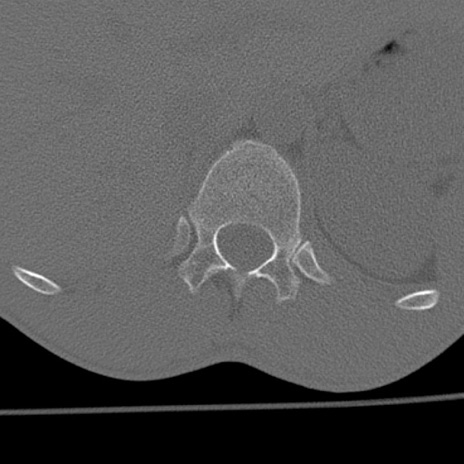

症例3 腰椎CT(横断像)

腰椎CT